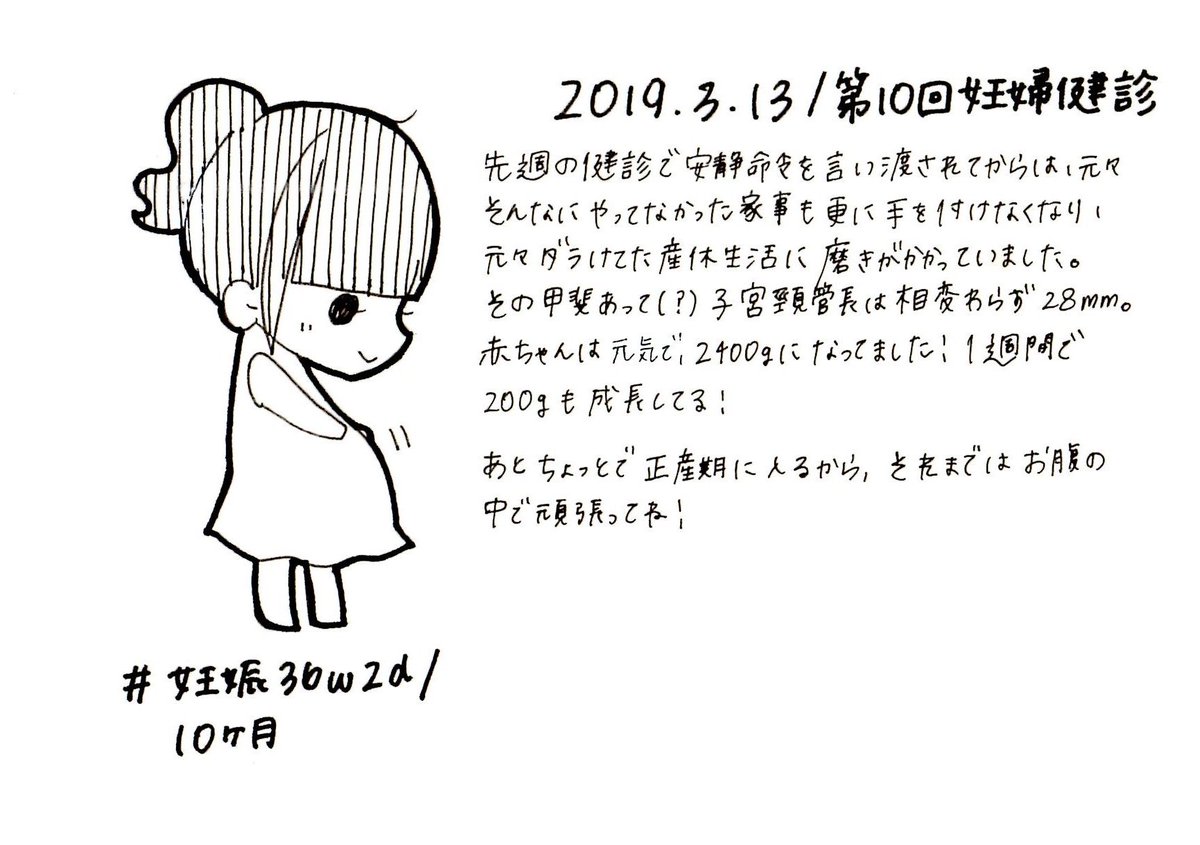

2019.3.13 第10回妊婦健診!子宮頸管長はまだ短いまま! エコー・お腹の写真載せます、閲覧注意! #育児漫画 #育児日記 #妊娠 #臨月 #妊娠10ヶ月 #妊婦健診 #子宮頸管長 #切迫早産 #ママ垢さんと繋がりたい #オリジナル漫画 #絵描きさんと繫がりたい pic.twitter.com/iAcjjTibIK

2019-09-04 18:57:57 拡大

拡大

拡大

拡大